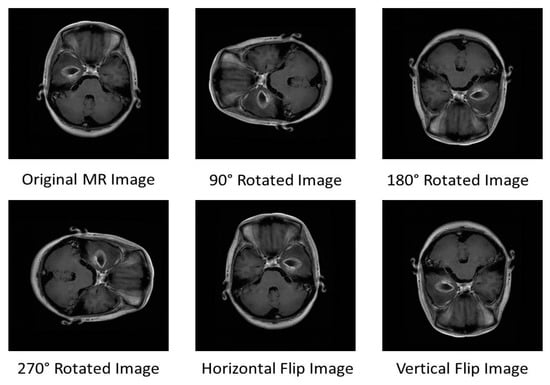

The fundamental task of the pre-processing step is to enhance the quality of the brain MR images and to improve the contrast. Generally, the brain MR images are acquired from various modalities which reduce the intensity level and produce artifacts. Therefore, contrast enhancement of brain MR images is important before further processing through human or computer vision systems [36]. Furthermore, preprocessing step can help to increase the signal-to-noise ratio, remove background noise, to preserve the edges of the MR images. Therefore, we use the contrast stretching algorithm in the pre-processing to produce high-resolution contrast MR images. The deep neural network models can enhance their learning capability and predict more accurate output with a large training dataset [37]. We utilize data augmentation techniques in order to get large training data from the original dataset. This helps in reducing the over-fitting effect that arises during training. Basically, rotations and flipping are used as data augmentation techniques for the generation of the large training dataset. Each image in the original dataset can be rotated with an angle of 90, 180, and 270 degrees. Similarly, the image can be flipped vertically and horizontally. In this way, a large training dataset can be generated and given as input to the pre-trained DCNN architecture.

We use a publicly available brain MRI dataset called Figshare developed by Cheng et al. [38]. The dataset contains 3064 T1-weighted brain MRI slices of three different categories of tumor for example meningioma, glioma, and pituitary obtained from 233 patients. The dataset comprises 708 meningioma slices, 1426 glioma slices, and 930 pituitary slices. All images are stored in .mat format. The MRI slices are normalized with an intensity range between 0 to 1. Figure 2 shows three categories of brain tumors from the Figshare dataset. Figure 3 demonstrates the images obtained after the application of the data augmentation technique.

Figure 3. Images Obtained after Application of Data Augmentation Technique.

Processes 11 00679 g003